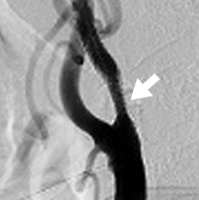

慢性期脳血管障害

脳血管障害の慢性期では、危険因子(高血圧、糖尿病、脂質異常症、喫煙など)の管理を行います。進行性の頸部内頸動脈狭窄症や高度狭窄に関してはステント留置術を行って脳梗塞の再発を予防してゆきます。診断はMRI/MRA、頚動脈エコー、造影CT(CTアンギオ)にて行います。

ステント留置後